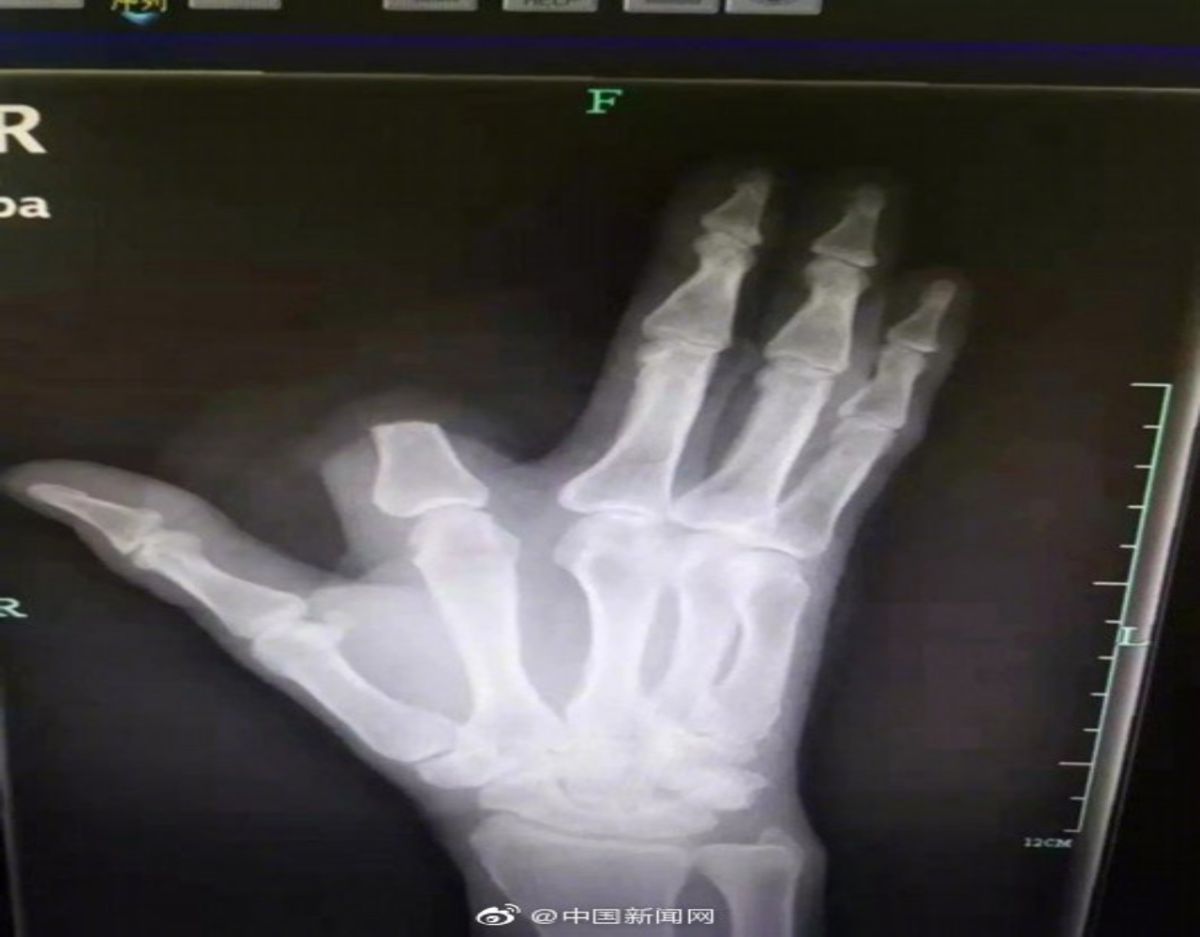

▲男子的反應讓醫師和許多大陸網友都傻眼。(圖/翻攝自大陸微博)